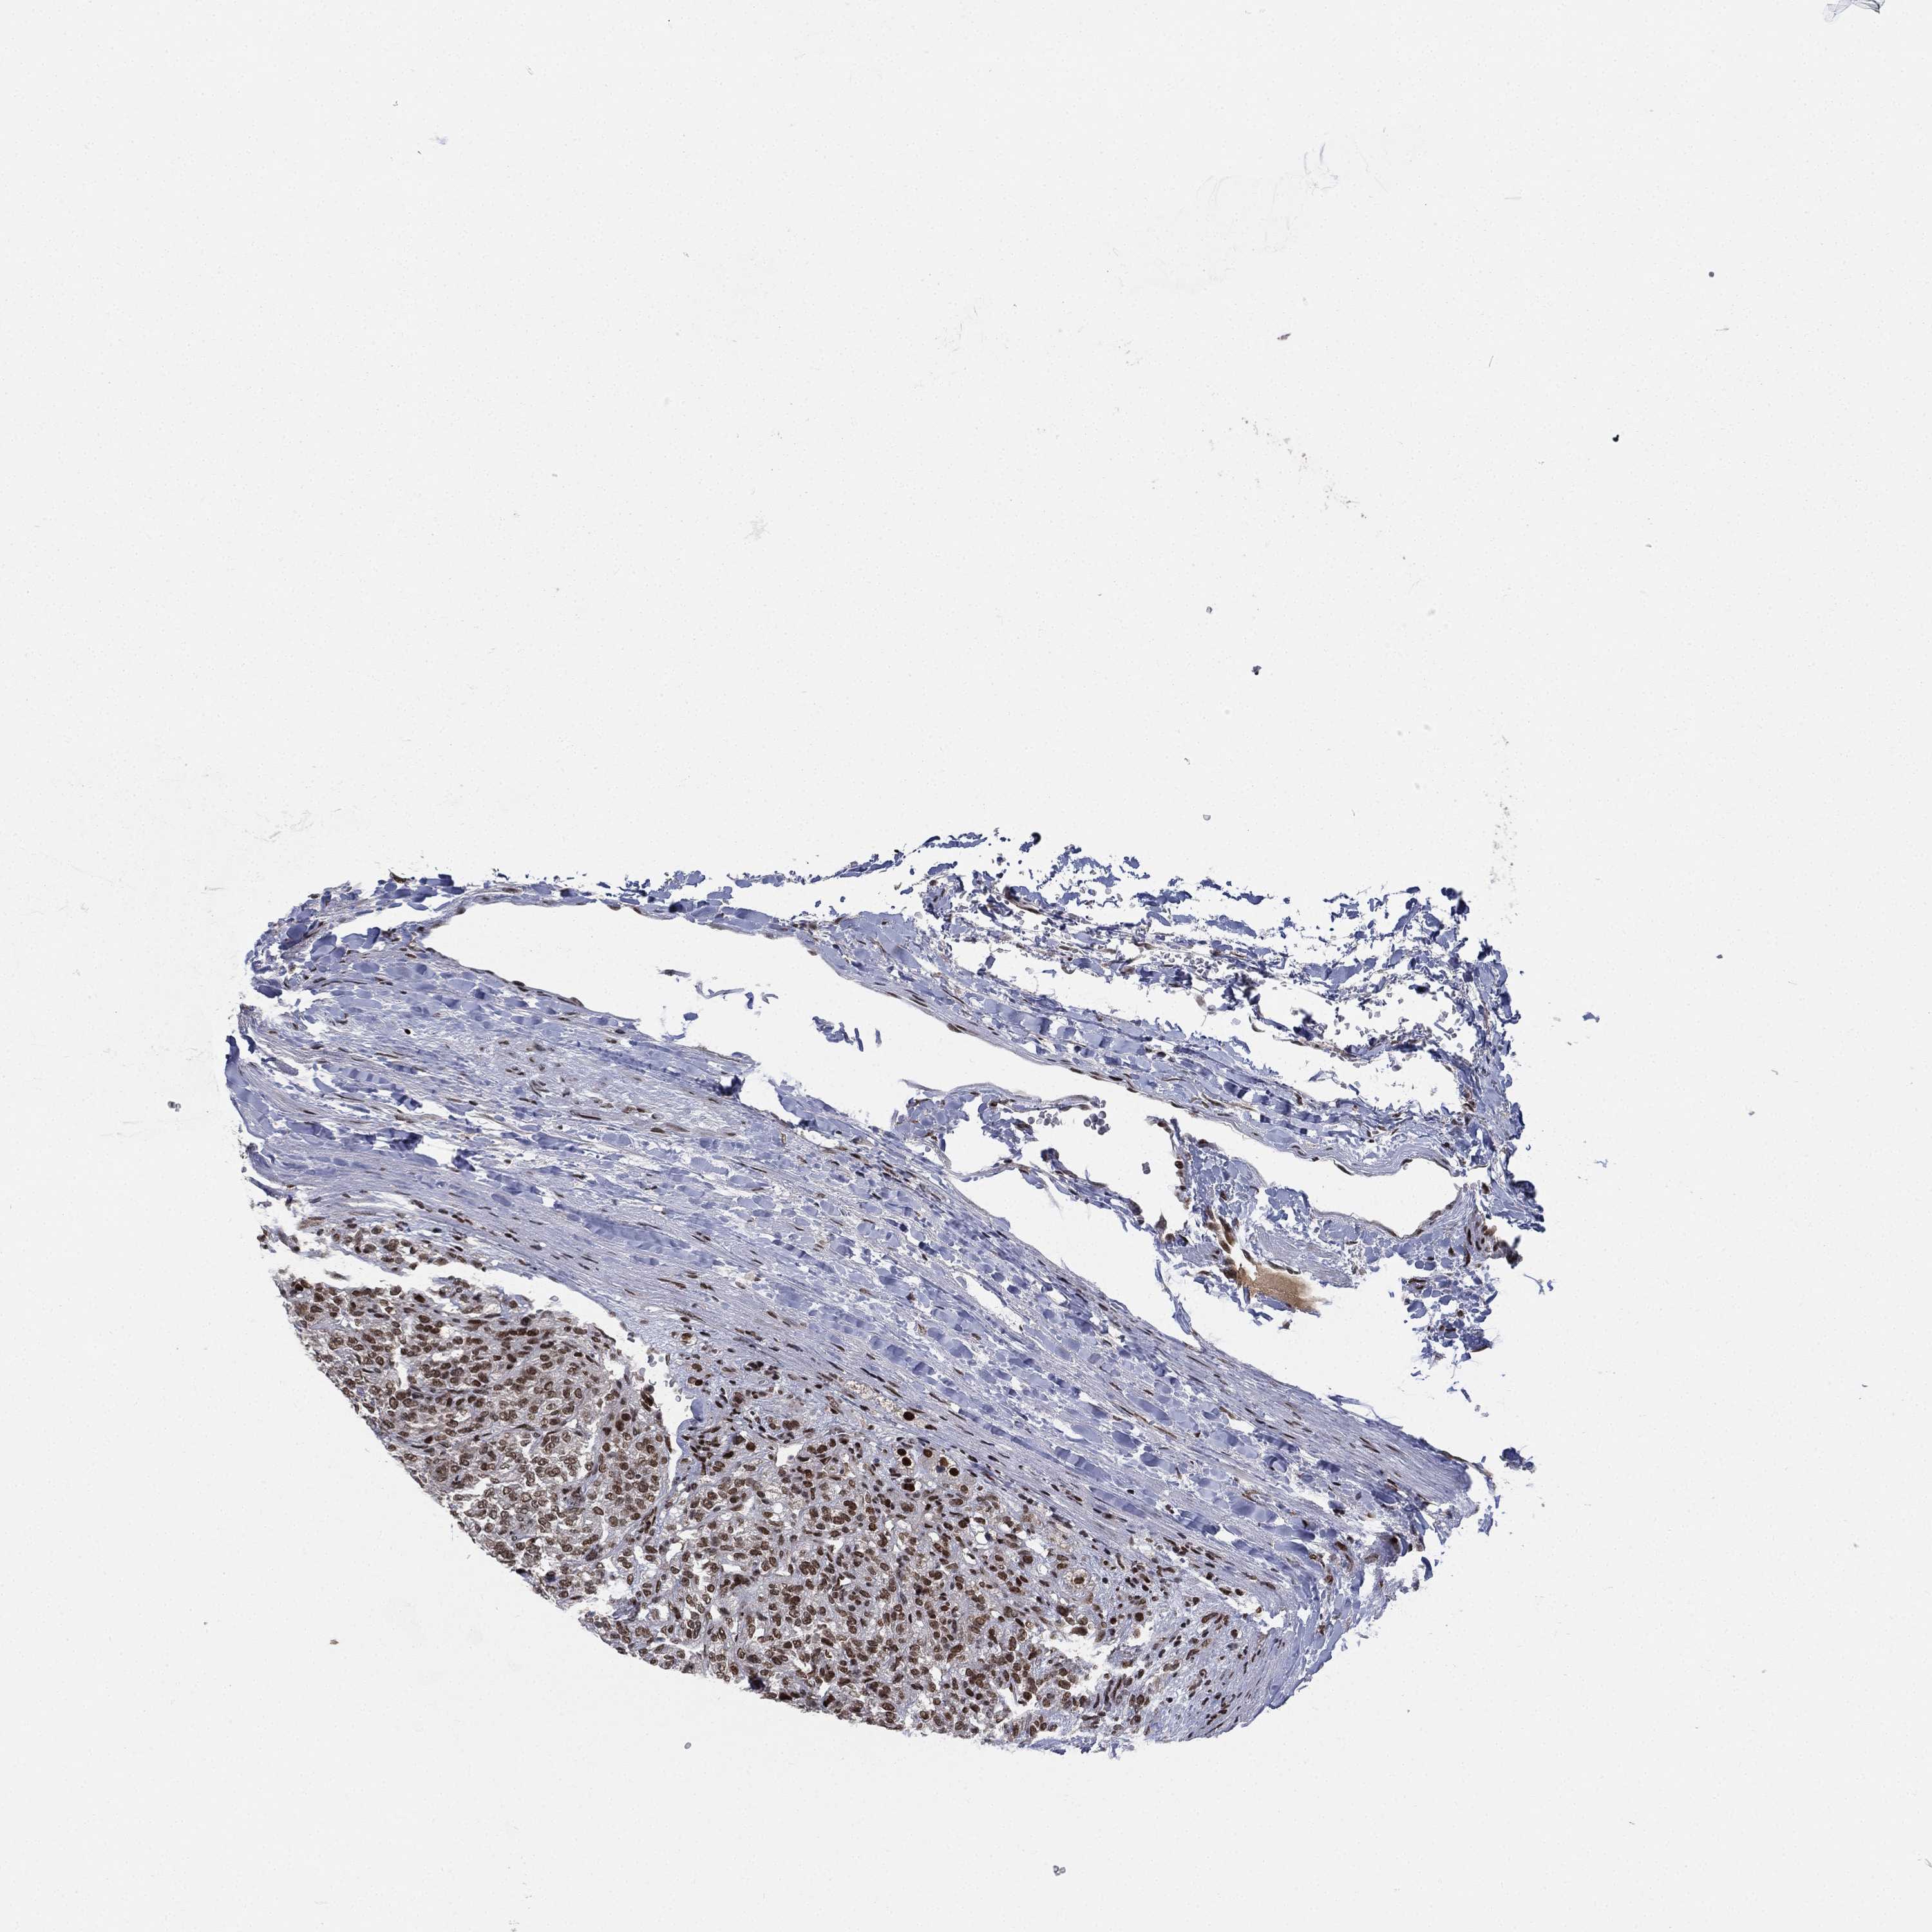

KIDNEY RENAL CLEAR CELL CARCINOMA (VALIDATION) - Interactive survival scatter ploti

The Survival Scatter plot shows the clinical status (i.e. dead or alive) for all individuals in the patient cohort, based on the same data that underlies the corresponding Kaplan-Meier plots. Patients that are alive at last time for follow-up are shown in blue and patients who have died during the study are shown in red.

The x-axis shows the expression levels (FPKM) of the investigated gene in the tumor tissue at the time of diagnosis. The y-axis shows the follow-up time after diagnosis (years). Both axes are complimented with kernel density curves demonstrating the data density over the axes. The top density plot shows the expression levels (FPKM) distribution among dead (red) and alive patients (blue). The right density plot shows the data density of the survived years of dead patients with high and low expression levels respectively, stratified using the cutoff indicated by the vertical dashed line through the Survival Scatter plot. This cutoff is automatically defined based on the FPKM cutoff that minimizes the p-score. The cutoff can be changed by dragging the vertical line or by entering a cutoff value in the square labeled "Current cut-off".

Under the Survival Scatter plot the p-score landscape (black curve; left axis) is shown together with dead median separation (red curve; right axis). Dead median separation is the difference in median mRNA expression between patients who have died with high and low expression, respectively. It is calculated as follows: median FPKM expression of dead patients with high expression - median FPKM expression of dead patients with low expression. This is intended to aid the user in visually exploring custom cutoffs and the associated p-scores and dead median separation.

Individual patient data is displayed and can be filtered by clicking on one or more of the category buttons on the top of the page. Categories describing expression level and patient information include: high, low, alive, dead, female, male and tumor stages. The scale of the x-axis can be toggled between linear and log-scale by clicking on the "x log" button. Mouse-over function shows TCGA ID, patient information and mRNA expression (FPKM) for each patient.

& Survival analysisi

Kaplan-Meier plots summarize results from analysis of correlation between mRNA expression level and patient survival. Patients were divided based on level of expression into one of the two groups "low" (under cut off) or "high" (over cut off). X-axis shows time for survival (years) and y-axis shows the probability of survival, where 1.0 corresponds to 100 percent.

RTF1 is not prognostic in Kidney Renal Clear Cell Carcinoma (validation)

Best expression cut offi

Based on the FPKM value of each gene, patients were classified into two groups and association between prognosis (survival) and gene expression (FPKM) was examined. The best expression cut-off refers the FPKM value that yields maximal difference with regard to survival between the two groups at the lowest log-rank P-value. Best expression cut-off was selected based on survival analysis .

When clicking on this number, the vertical dashed line indicating cut-off, the interactive survival plot, and the Kaplan-Meier curve will be adjusted to show results based on the best expression cut-off.

: 30.43

Median expressioni

Median expression refers to the median FPKM value calculated based on the gene expression (FPKM) data from all patients in this dataset. When clicking on this number, the vertical dashed line indicating cut-off, the interactive survival plot, and the Kaplan-Meier curve will be adjusted to show results based on the median expression.

: N/A

Median follow up timei

Median follow up time refers to the median time (years) after diagnosis with this type of cancer, based on clinical data from all patients in this dataset.

P scorei

Log-rank P value for Kaplan-Meier plot showing results from analysis of correlation between mRNA expression level and patient survival.

N/A

5-year survival highi

5-year survival for patients with higher expression than the expression cutoff.

For melanoma and glioma, 3-year survival is shown.

5-year survival lowi

5-year survival for patients with lower expression than the expression cutoff.

TCGA RNA samplesi

RNA-seq data is reported as average FPKM (number Fragments Per Kilobase of exon per Million reads), generated by the The Cancer Genome Atlas (TCGA) .

Normal distribution across the dataset is visualized with box plots, shown as median and 25th and 75th percentiles. Points are displayed as outliers if they are above or below 1.5 times the interquartile range. FPKM values of the individual samples are presented next to the box plot.

Average pTPM 24.8

Number of samples 100